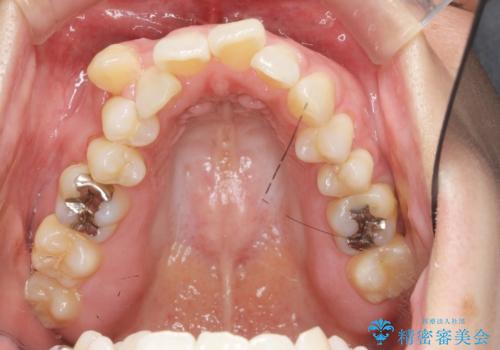

職業柄ワイヤー矯正ができない、マウスピース矯正で行う八重歯抜歯症例

- 「長年気になっている八重歯を矯正治療で治したい、ただし職業柄ワイヤー矯正は絶対にできないのでマウスピース矯正を希望。」

、と矯正治療を希望され来院されました。

通常は八重歯の抜去は行わず、小臼歯の抜去を行いワイヤー矯正を行いますが、八重歯を抜去することでマウスピースで現実的に達成できる機能的な歯並びを獲得できるよう治療計画を立案します。